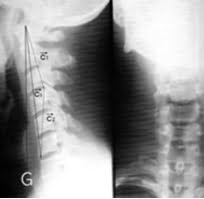

목 척추병증

심한 연성 추간판 탈출증, 후종 인대 골화증(OPLL)이나 경추의 척추증(spondylosis)에 이차적으로 발생.